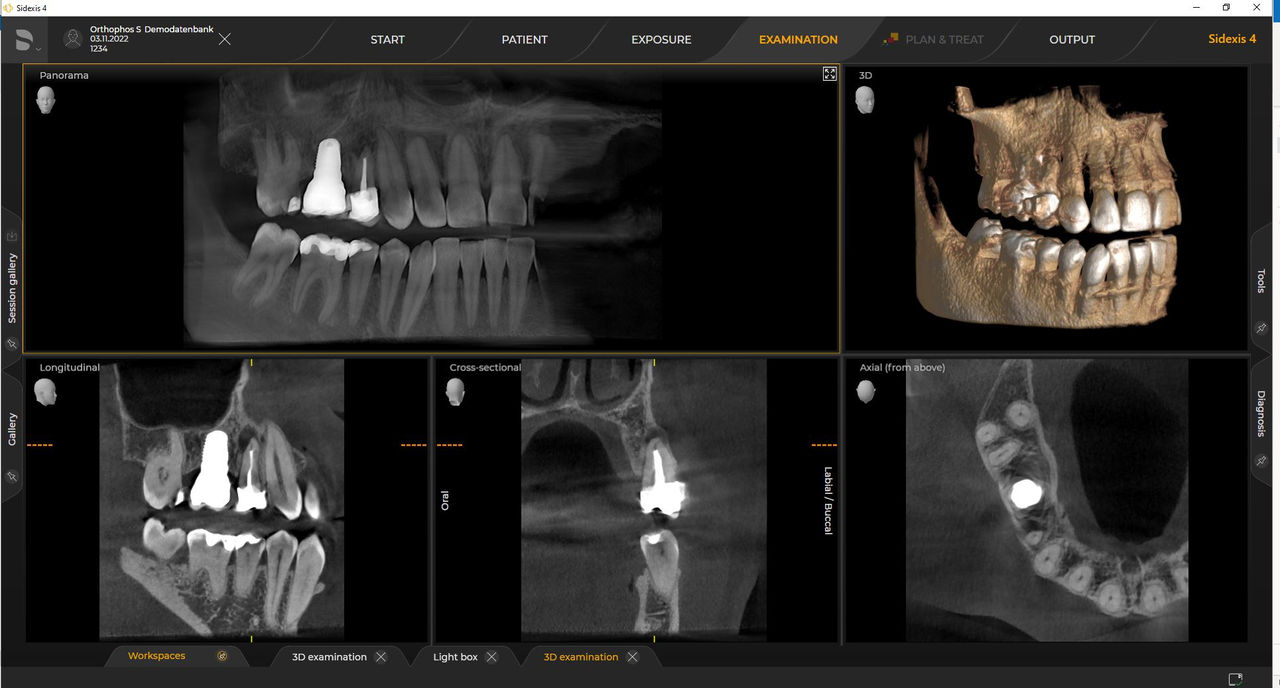

Las unidades de radiología de Dentsply Sirona funcionan exclusivamente con Sidexis 4. Sin embargo, la migración de datos de Sidexis XG a Sidexis 4 es muy fácil. Sidexis 4 permite una experiencia digital completa con las últimas herramientas

Orthophos S de 2D permite una actualización 3D. Axeos es una unidad híbrida exclusiva. El Orthophos E no ofrece esta opción.